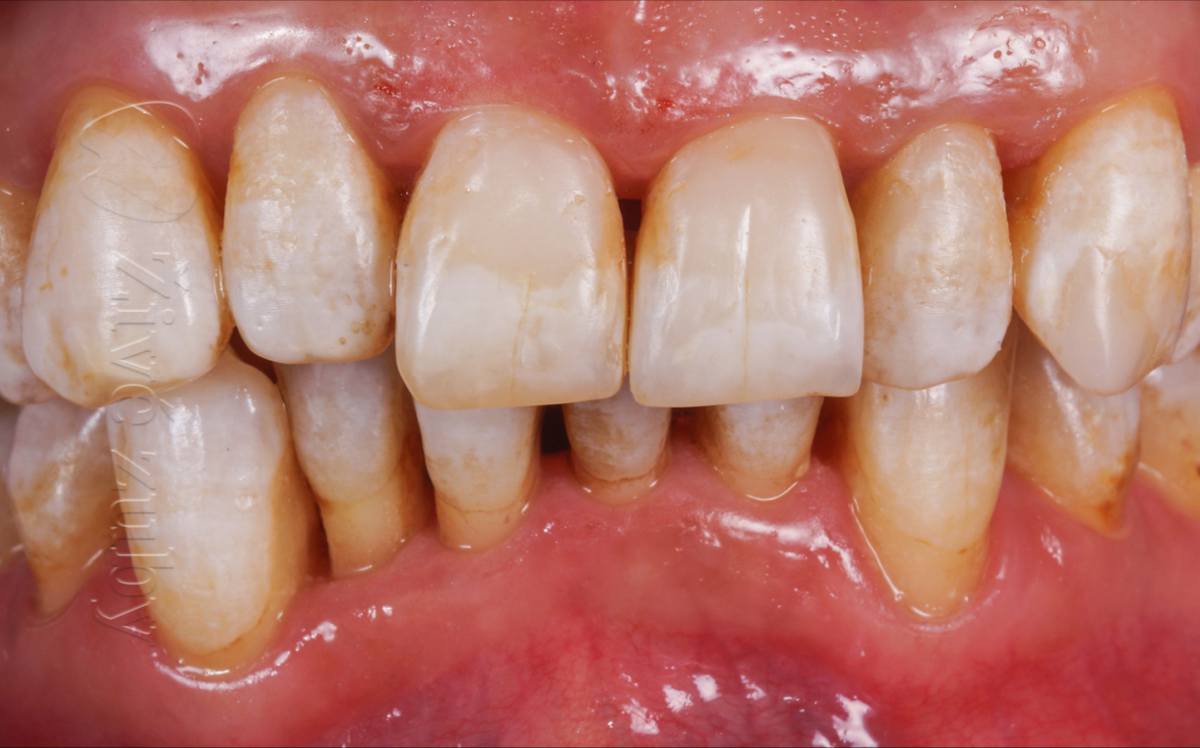

Mikroabraze a Infiltrace skloviny

(Ošetření Fluorózy a podobných lézí, demineralizaci skloviny, …)

Výchozí stav  ——- Kontrola po 2 letech